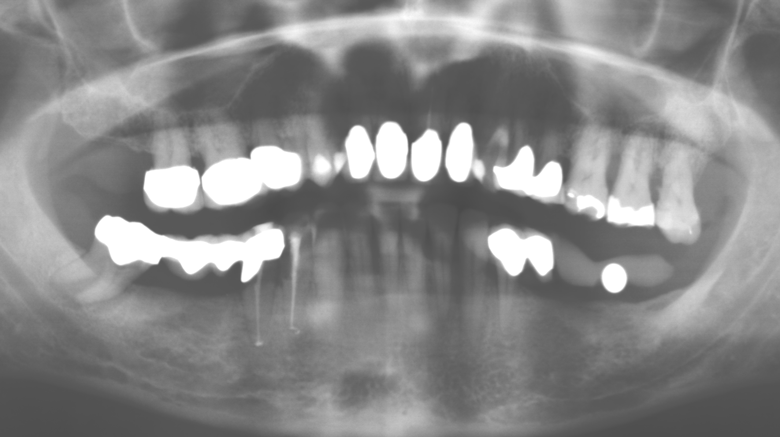

Eine 52-jährige Patientin stellte sich nach Zahnverlust im 3. Quadranten erstmals 2004 vor. Sie hatte den Wunsch nach einer prothetischen Neuversorgung. Im Rahmen der parodontologischen und radiologischen Diagnostik zeigte sich ein ausgeprägter parodontologischer Behandlungsbedarf. Die Zähne 48, 28, 27 zeigten zudem eine infauste Prognose und wurden entfernt (Abb. 1). Nach der erfolgreich abgeschlossenen systematischen PARTherapie wurde eine festsitzende implantatprothetische Versorgung mit Insertion von fünf Implantaten in Regio 35, 36, 37 und 46, 47 durchgeführt. Die prothetische Versorgung der natürlichen Zähne erfolgte mit verblendeten Zirkonoxidkeramikkronen, die Implantate wurden mit zweiteiligen individuellen Zirkonoxidabutments und ebenfalls verblendeten Kronen aus einer Zirkonoxidkeramik versorgt (Cercon base colored, Dentsply Sirona Lab). Die definitive Insertion der prothetischen Versorgung erfolgte im Jahr 2005.

Im Rahmen der ZehnJahresKontrolle zeigten sich keine Hinweise auf einen fortschreitenden parodontalen Attachmentverlust oder einen periimplantären Knochenverlust (Abb. 3).